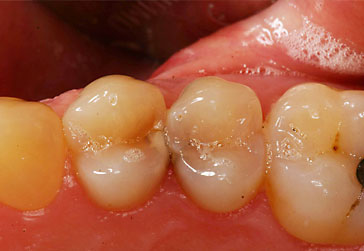

Zahnzwischenraumkaries

![]() |

Während Vorstufen einer Karies noch ohne invasive Eingriffe mittels Fluoridierungsverfahren behandelt werden können, werden kleinere kariöse Stellen vorzugsweise mit minimalinvasiven Präparationstechniken besonders substanzschonend versorgt. Dabei ist nicht allein die klein ausfallende Füllung, sondern die streng defektbezogene Kariesentfernung von Bedeutung.